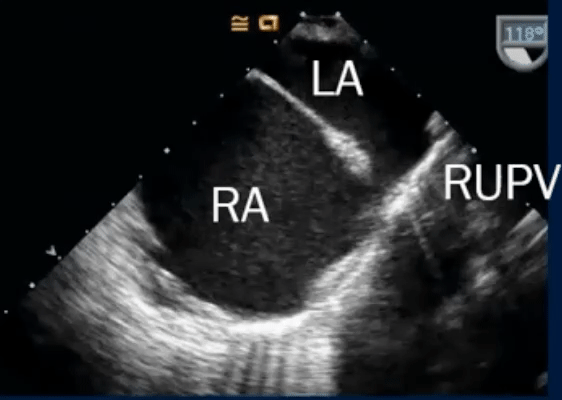

- TEE

- Associated with PAPVR (RUPV > RMPV/RLPV)

- Can be difficult to see on TTE, ∴ TEE, CMR, or CT needed.

- TEE below shows bicaval view. To identify the superior sinus venosus defect (i.e. SVC type), you’ll want to pay attention to the SVC area as highlighted in this image.